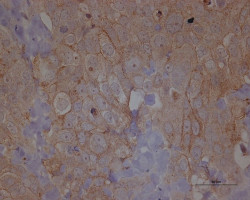

El colágeno juega un papel protector durante el desarrollo del cáncer de páncreas

En contra de lo que se creía desde hace tiempo, el colágeno de tipo I producido por los fibroblastos asociados al cáncer no favorece el desarrollo del cáncer, sino que desempeña una función protectora en el control de la progresión del cáncer de páncreas, informa un nuevo estudio de investigadores del MD Anderson Cancer Center de la Universidad de Texas. Este nuevo conocimiento respalda nuevos enfoques terapéuticos que refuerzan el colágeno en lugar de suprimirlo.